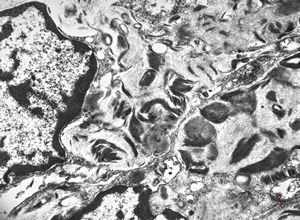

F, 8y. | metachromatic leukodystrophy … n. suralis